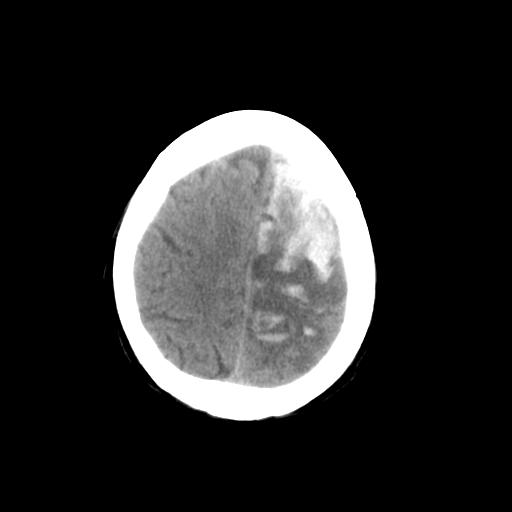

男,78岁。自诉两周前因右侧肢体障碍行ct检查,诊断为脑梗塞(患者ct片已丢失)治疗好转后出院。现因意不清12小时,又行ct检查。

结合病史考虑左侧额颞顶叶出血性脑梗塞。

结合病史考虑左侧额颞顶叶出血性脑梗塞